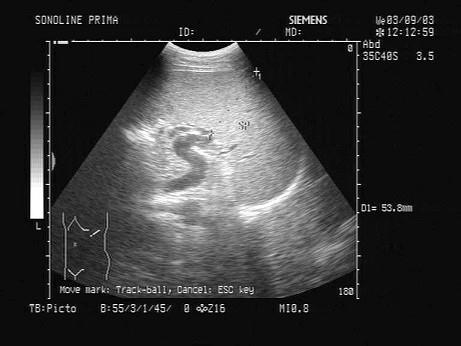

问题 某患者脾脏声像图表现如图,诊断为?(?)

选项 A.正常脾脏 B.脾大 C.脾破裂 D.脾梗死 E.以上都不是

答案 B